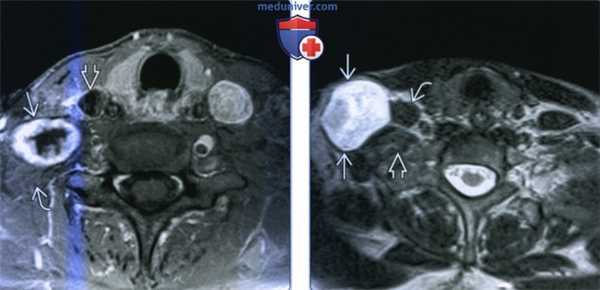

(Слева) МРТ Т1ВИ FS с КУ, аксиальная проекция. Крупная шваннома в нижней части шеи справа, которая лежит на средней лестничной мышце. Отмечается неравномерное накопление контраста по периферии опухоли. Центральная область, не накапливающая контраст, представляет собой участок кистозной дегенерации. При поражении нижних шейных лимфоузлов патологический очаг обычно расположен медиальнее, возле внутренней яремной вены.

(Справа) MPT Т2ВИ, аксиальная проекция. В нижней части шеи визуализируется шваннома сигнал гетерогенный гиперинтенсивный. Опухоль, расположенная в паравертебральном пространстве, раздвигает и деформирует переднюю и среднюю лестничные мышцы.